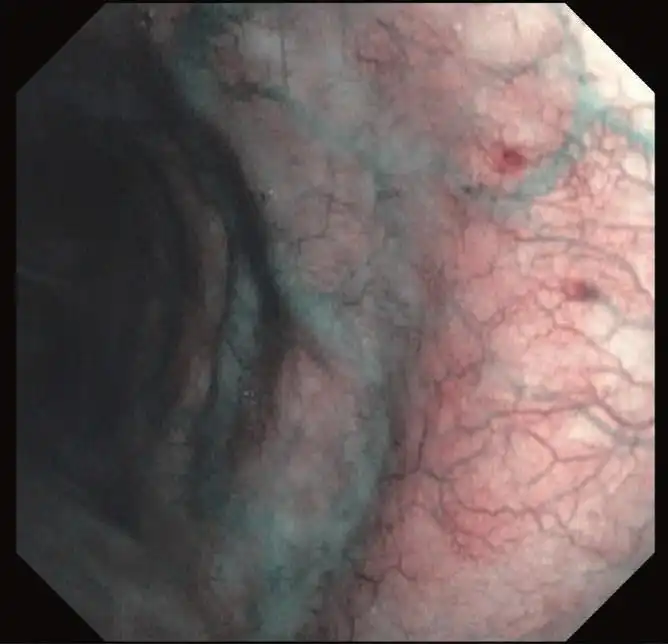

NBI(窄带成像)

NBI是一种光学图像增强技术,可改善粘膜表面血管的可视化